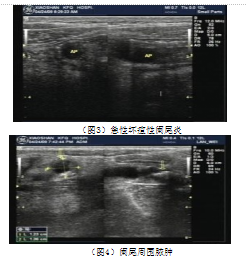

急性阑尾炎彩色多普勒超声影像图像特征及诊断

246x258 - 65KB - PNG